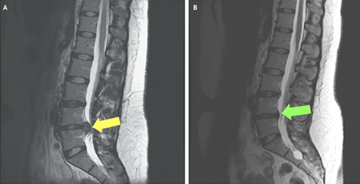

• Magnetic resonance imaging (MRI) – MRI scans provide clear images of soft tissues, including discs and nerves, and are the most common test used to confirm a disc herniation.